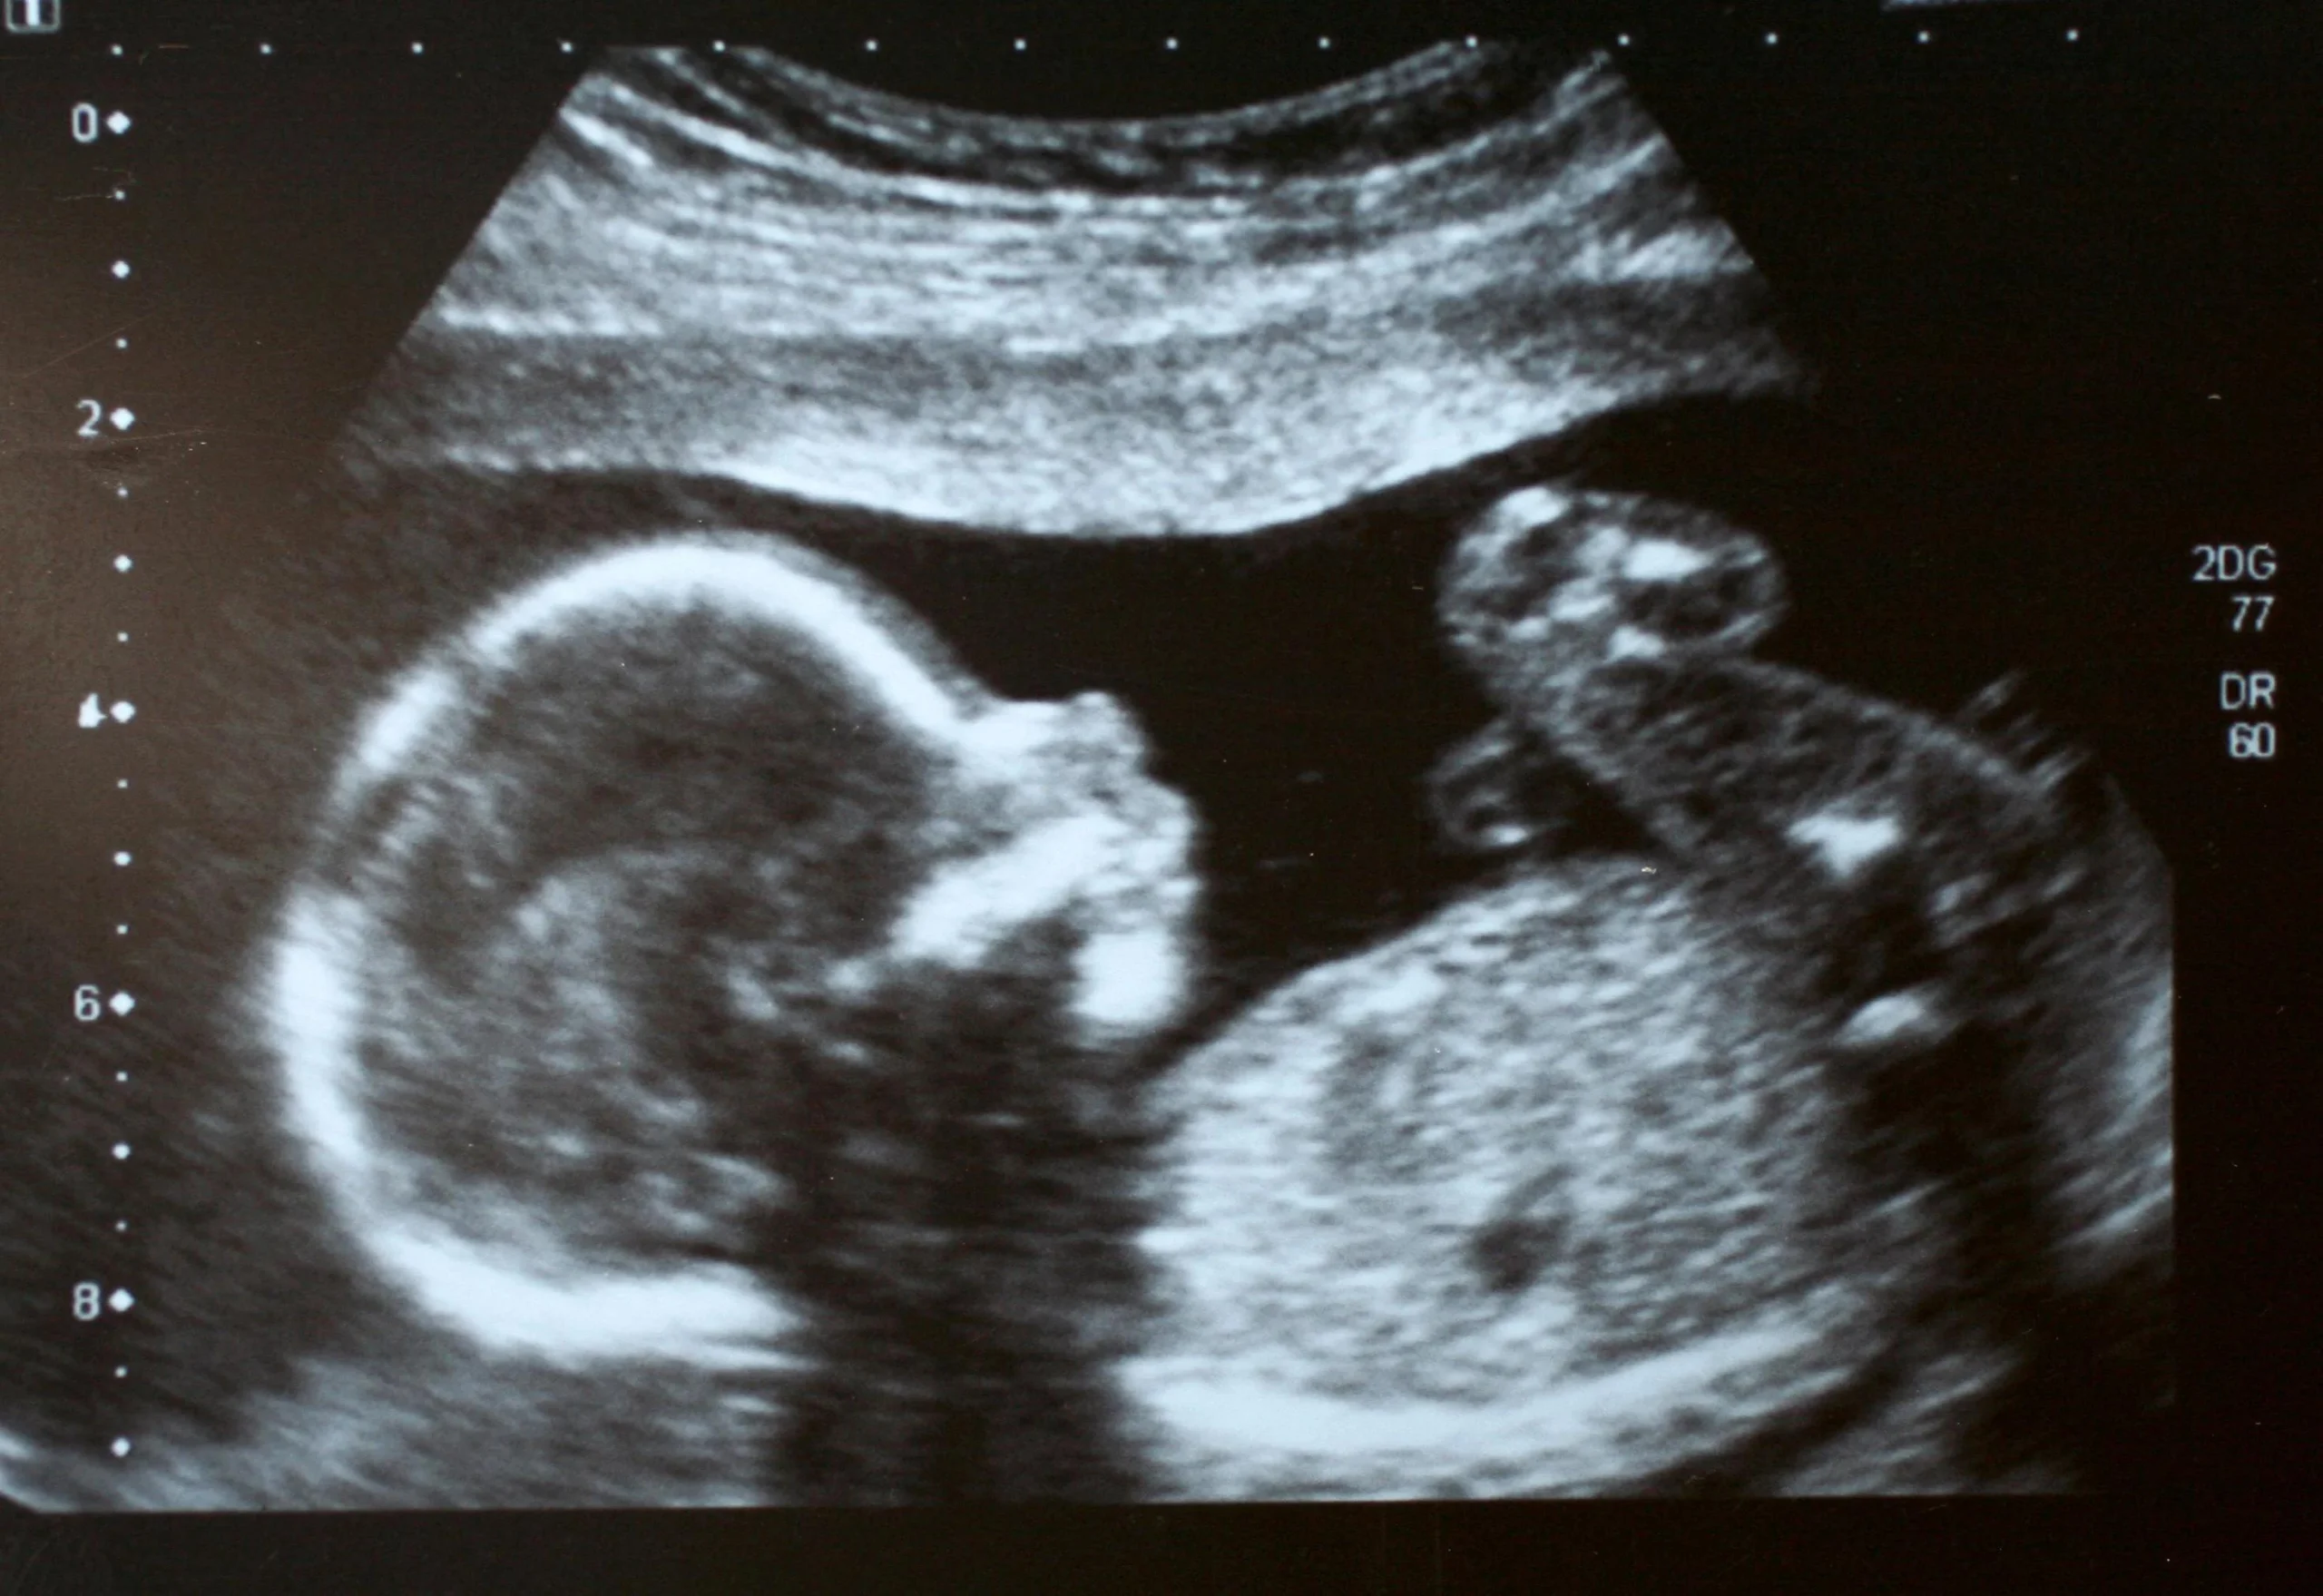

Was kann man mit dem Ultraschall in der Schwangerschaft erkennen?

Mit dem Ultraschall können verschiedene Dinge in der Schwangerschaft erkannt werden, darunter:

- Zwillinge oder Mehrlinge: Der Ultraschall kann feststellen, ob es sich um eine Mehrlingsschwangerschaft handelt.

Bei einer Ultraschalluntersuchung wird ein Schallkopf auf den Bauch gelegt. Der Schallkopf sendet Schallwellen aus, die von den Organen im Körper reflektiert werden. Die reflektierten Schallwellen werden von einem Computer verarbeitet und auf einem Bildschirm angezeigt.

Was sind die Vorteile von 3D-Ultraschall in der Schwangerschaft?

3D-Ultraschall bietet eine detailliertere Darstellung des Kindes im Mutterleib als 2D-Ultraschall. 3D-Ultraschall kann verwendet werden, um die Entwicklung des Kindes genauer zu beurteilen und Fehlbildungen frühzeitig zu erkennen.